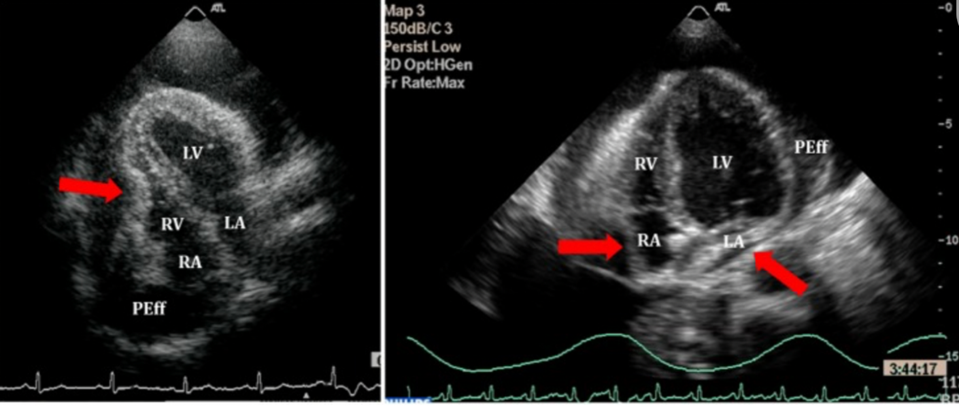

По данным ЭхоКГ при тампонаде сердца выявляются следующие изменения: «плавающее» сердце», ранний диастолический коллапс правого желудочка, поздний диастолический коллапс правого предсердия, расширение нижней полой вены, которая практически не спадается на вдохе, аномальное движение межжелудочковой перегородки, повышенная дыхательная вариабельность (>25%) скорости митрального потока, снижение на вдохе и повышение на выдохе прямого диастолического потока в лёгочных венах, дыхательная вариабельность объёмов желудочков, скорости потока в аорту (видимость парадоксального пульса по ЭхоКГ) и переполнение нижней полой вены) [30] (рисунок 3).

Рисунок 3. ЭхоКГ при тампонаде сердца: коллапс правого желудочка (слева), коллапс правого и левого предсердий (справа) [31].